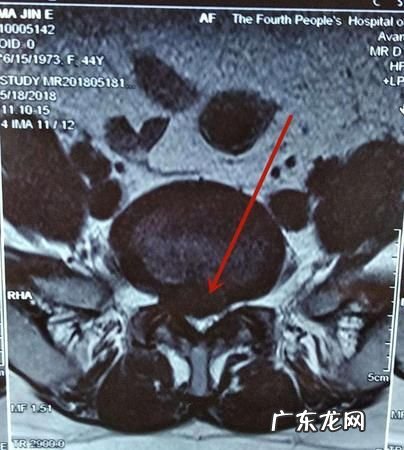

磁共振诊断报告书写规范没看片子不好说,现在的报告越来越抽象了,原来还描述一下病灶的形态大?。?现在什么都没有 。

猜一下 , 胸11椎体内有几种可能,骨肿瘤,骨结核;

胸1-2椎间盘轻度突出;硬膜囊受压;黄韧带肥厚 。

肝内囊肿 。